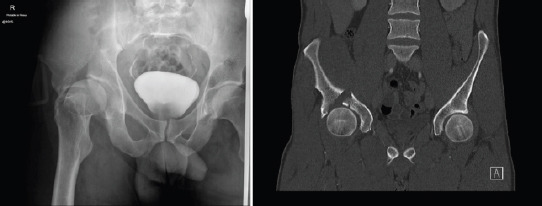

A 31-year-old patient was involved in road traffic collision and suffered an isolated injury to his right hemipelvis. The patient was clinically neurovascularly intact with Ankle Brachial Index normal for both lower extremities. Pelvic radiographs showed an anterior hip dislocation and a right acetabular fracture (Fig. 1a). The hip was relocated and the subsequent total body Computed Tomography (CT) scan revealed a fracture of the AC of the acetabulum along with anterior dome acetabular impaction (Fig. 1b). The CT Scan also revealed an intimal injury of the right common femoral artery (CFA) at the level of the inguinal ligament. The right lower limb arterial duplex revealed a dissection flap on the posterior wall of the CFA, which caused no significant velocity ratios with stable appearance and no extravasation. Non-operative management of the CFA injury was advised by the vascular surgery team.

Figure 1.

(a) Anteroposterior pelvic radiograph showing the anterior hip dislocation, the anterior column fracture, and the anterior dome impaction (b) Frontal computed tomography scan view depicting the anterior dome impaction and the column fracture.